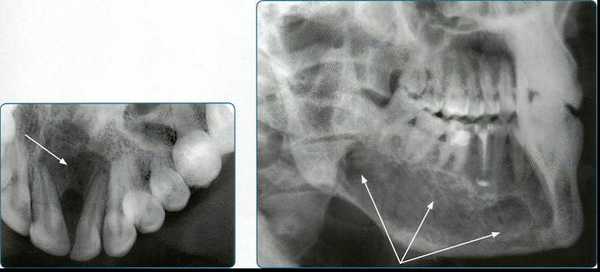

4. Панорамная томография

Более трех десятилетий назад в арсенал рентгенодиагностики заболеваний зубочелюстной системы, ЛОР-органов и других отделов черепа вошла панорамная рентгенография. При этом методе исследования аппликатор рентгеновской трубки вводят в рот пациента, а кассета располагается вокруг верхней или нижней челюстной дуги. В обоих случаях пациент придерживает кассету с наружной стороны ладонями, плотно прижимая ее к мягким тканям лица.

Проводится также и боковая панорамная томография, на боковом панорамном снимке одновременно отображаются зубы верхнего и нижнего ряда каждой половины челюсти.

Прямые панорамные рентгенограммы имеют преимущество перед внутриротовыми снимками по богатству деталями изображения костной ткани и твердых тканей зубов. При минимальной лучевой нагрузке они позволяют получить широкий обзор альвеолярного отростка и зубного ряда, облегчают работу рентгенолаборанта и резко сокращают время исследования. На этих снимках хорошо видны полости зуба, корневые каналы, периодонтальные щели, межальвеолярные гребни и костная структура не только альвеолярных отростков, но и тел челюстей. На панорамных рентгенограммах выявляются альвеолярная бухта и нижняя стенка верхнечелюстной пазухи, нижнечелюстной канал и основание нижнечелюстной кости.

На основании панорамных снимков диагностируют кариес и его осложнения, кисты разных типов, новообразования, повреждения челюстных костей и зубов, воспалительные и системные поражения. У детей хорошо определяется состояние и положение зачатков зубов.

5. Ортопантомография

Панорамная зонография, или, как ее чаще называют, ортопантомография, явилась своего рода революцией в рентгенологии челюстно-лицевой области и не имеет себе равных по ряду показателей (обзор большого отдела лицевого черепа в идентичных условиях, минимальная лучевая нагрузка, малые затраты времени на исследование).

Панорамная зонография позволяет получить плоское изображение изогнутых поверхностей объемных областей, для чего используют вращение рентгеновской трубки и кассеты.

Преимуществом ортопантомографии является возможность демонстрировать межчелюстные контакты, оценивать Результаты воздействия межчелюстной нагрузки по состоянию замыкающих пластинок лунок и определять ширину периодонтальных путей.

Ортопантомограммы демонстрируют взаимоотношения зубов верхнего ряда с дном верхнечелюстных пазух и позволяют выявить в нижних отделах пазух патологические изменения одонтогенного генеза.

Особенно важно использовать ортопантомографию в детской стоматологии, где она не имеет конкурентов в связи с низкими дозами облучения и большим объемом получаемой информации. В детской практике ортопантомография помогает диагностировать переломы, опухоли, остеомиелит, кариес, периодонтиты, кисты, определять особенности прорезывания зубов и положение зачатков.